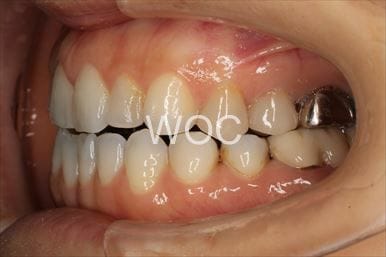

開咬開咬

上下舌側矯正を希望。上顎両側第一小臼歯の抜歯としたが上顎右側第二小臼歯は治療した歯であったため、抜歯部位を変更。治療の難度が上がったため治療期間が少し延長しました。

- 年齢:33歳女性

- 主訴:出っ歯、前歯で噛めない

- 基本矯正料金:1,295,000円

- 治療期間:2年8ヶ月

- 抜歯部位:上顎右側第二小臼歯、左側第一小臼歯